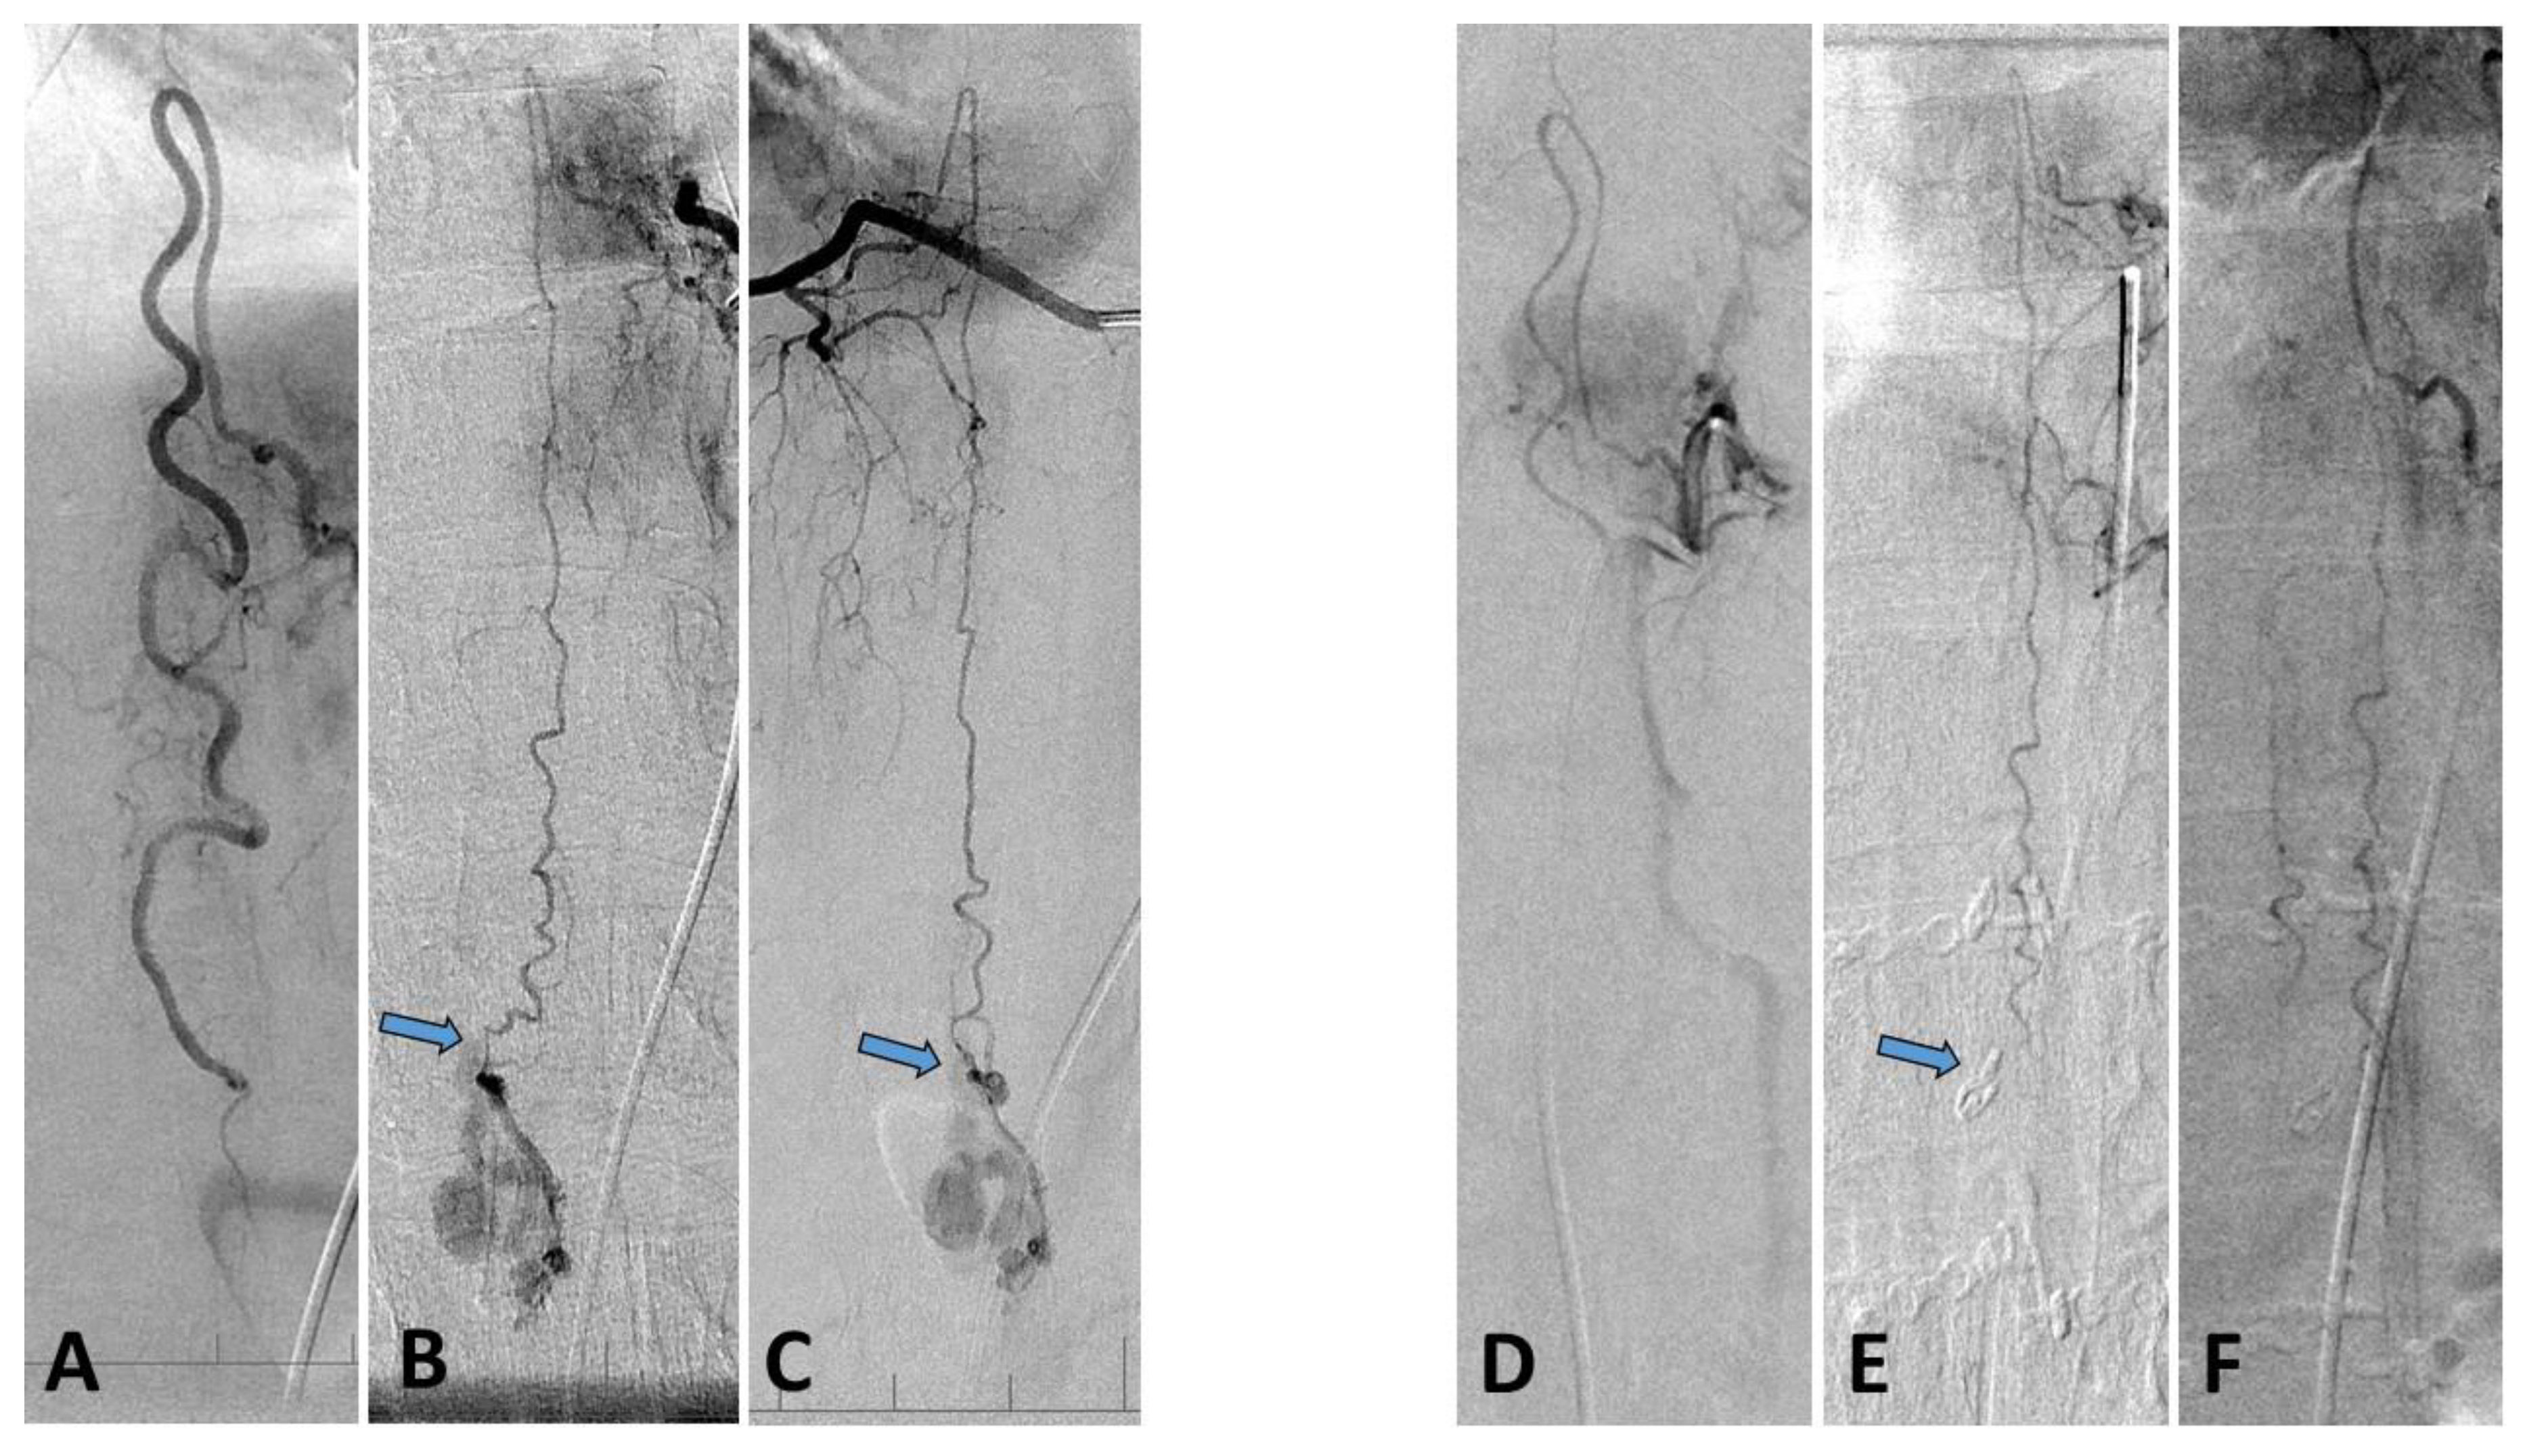

2. Case Report